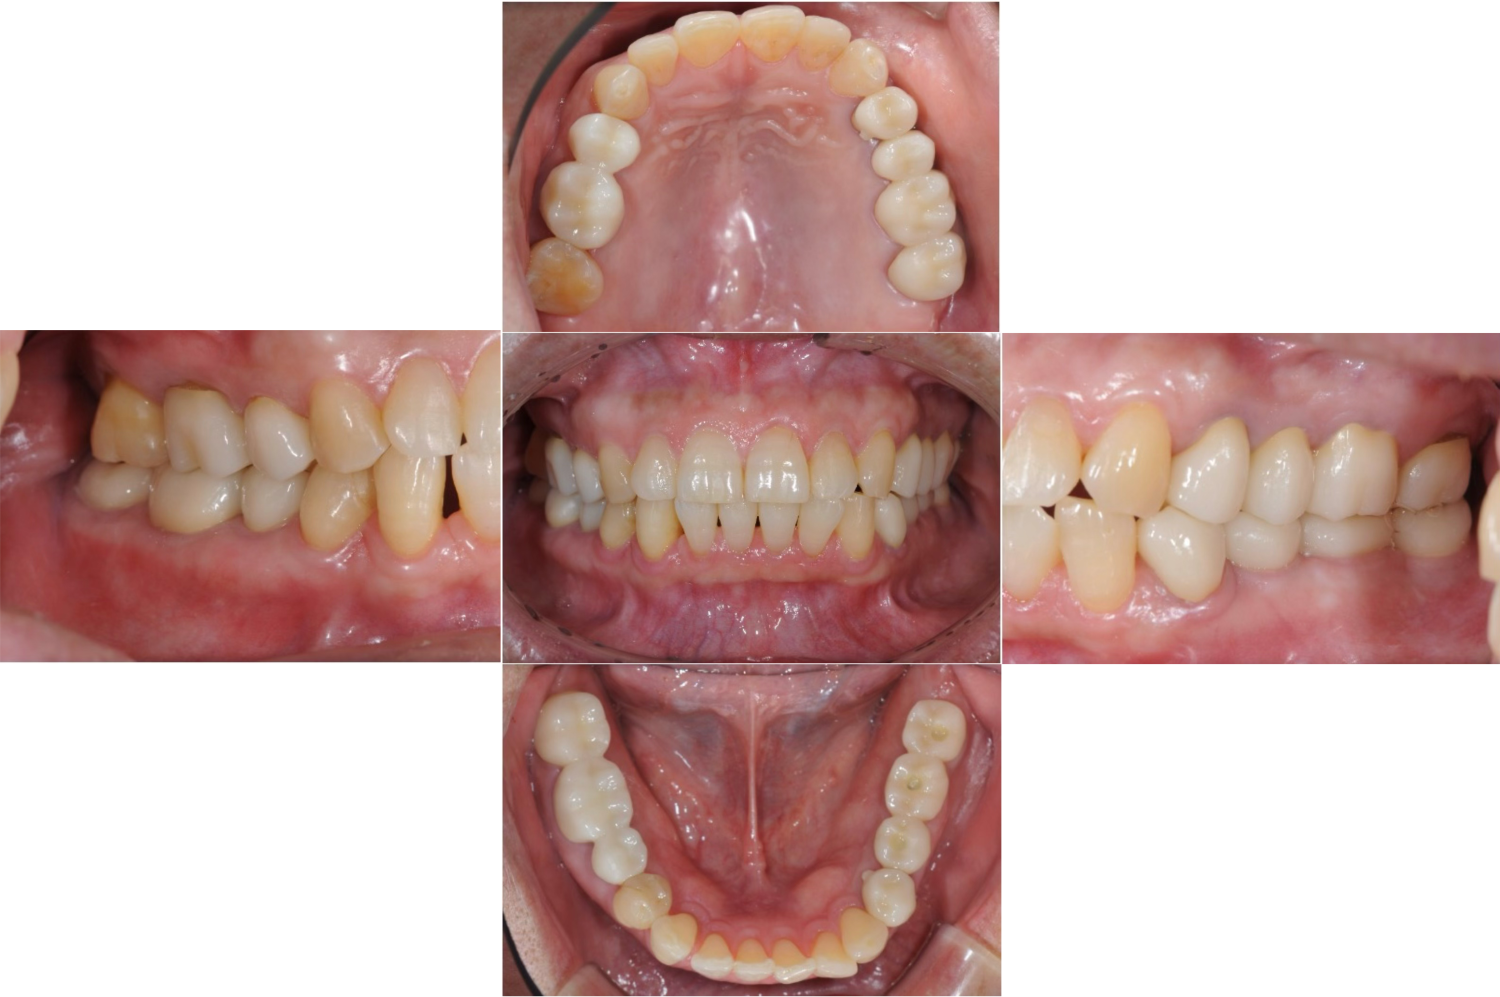

| 主訴 | 全顎治療希望、右下の歯が動いて痛いので噛みずらい。当院でインプラント治療したお母様からの紹介 |

| 治療内容 | プラークコントロール不良なため歯周治療を行い、保存不能の歯を抜歯し、抜歯窩の治癒を待って、欠損部にインプラントを施し咬合再構成を行う。 プロビジョナルレストレーションによる咬合関係を模索した後、全顎にわたりセラミックによる補綴治療、その後メインテナンスに移行 |

| 想定されたリスク | 食いしばり(パラファンクション)によるセラミックの破折、歯の破折 |